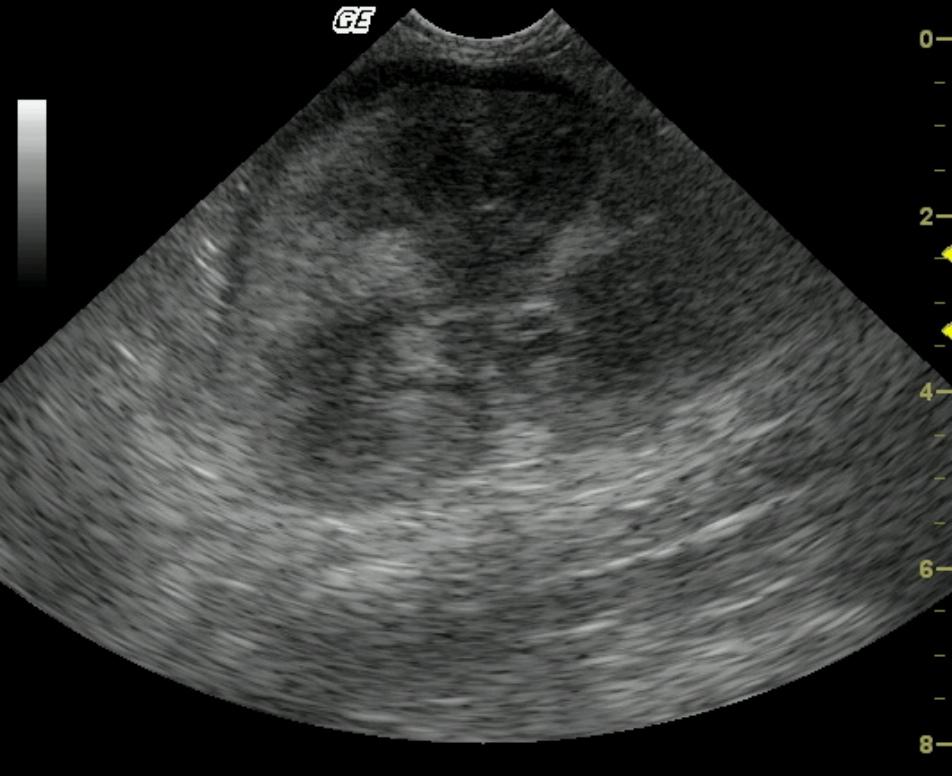

This 3-year-old MN DSH was presented for weight loss. The physical exam revealed hypothermia and palpably enlarged kidneys. A CBC and blood chemistry profile demonstrated severe azotemia that decreased after fluid therapy. Moderate anemia was also present.